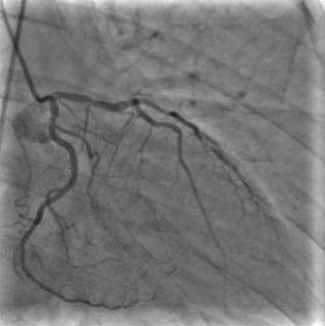

X-ray angiography is the most used imaging modality to visualise blood vessels for interventional purposes such as stenting of stenosed vessels or for diagnostic purposes such as assessment of myocardial perfusion or stenosis grading. To minimise ionising radiation exposure of the patient and medical personnel during image acquisition, low power X-Rays are used resulting in noisy and low contrast images. In the context of diagnosis, the main object of interest is the vascular tree, its branchings and variations in thickness. It is therefore necessary to accurately highlight the vessels in consecutive frames to reduce the noise and improve contrast. In addition, in interventional procedures, identifying interventional instruments (catheter, wires) is also needed in order to better plan and control their positioning. Efficiently discriminating between instruments and vessels as well as other anatomical structures that may have similar appearance is crucial during the interventions. Figure 1(a-c) shows an example of an angiogram sequence. Note large non-rigid motion between frames as well as the ambiguity between vessels and the catheter. Figure 1(e) shows a frame from a different sequence of the same patient but taken at different scan and angle and (f) shows a different patient. There is a significant difference in vessel as well as catheter locations in all three sequences, which we consider as independent examples. Figure 1(d) shows the ground truth segmentation of the first frame.

The dataset consists of anonymised fluoroscopy X-Rays of 26 different patients. The images were acquired during stent placement using a General Electric Innova 2000 system and stored according to standard medical protocol in DICOM format. In total the dataset includes 36000 frames corresponding to 365 distinct video sequences with an average of 98 frames each. Different sequences of the same patient were taken at different angles and stages of the procedure therefore they differ significantly as shown in Figure 1(c)(e)(f). Each frame is rescaled from to due to memory constraints.